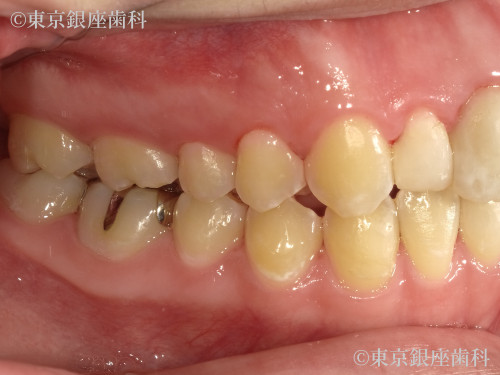

Before

20代 女性

疾患 矯正

施術内容 矯正

治療期間 1年1ヶ月 費用 90万円(税込)

インビザライン:コンプリヘンシブパッケージ